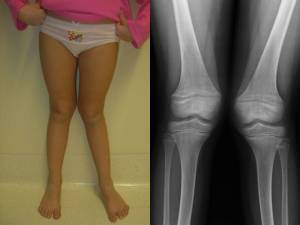

Fig 1: ginocchia a X

Consiste in un eccessivo aumento dell’angolo a vertice interno formato dall’asse del femore e della tibia, le cosiddette ginocchia a X (fig 1). Fino a 3-4 anni il ginocchio valgo può essere considerato fisiologico, in relazione anche con la lassità legamentosa e l’ipotonia muscolare tipiche di questa età. In seguito si verifica spontaneamente una progressiva correzione della deformità, di solito verso i 6-7 anni (fig. 2A-2B).

- Fig. 2: giocchio valgo fisiologico a 3 e a 6 anni